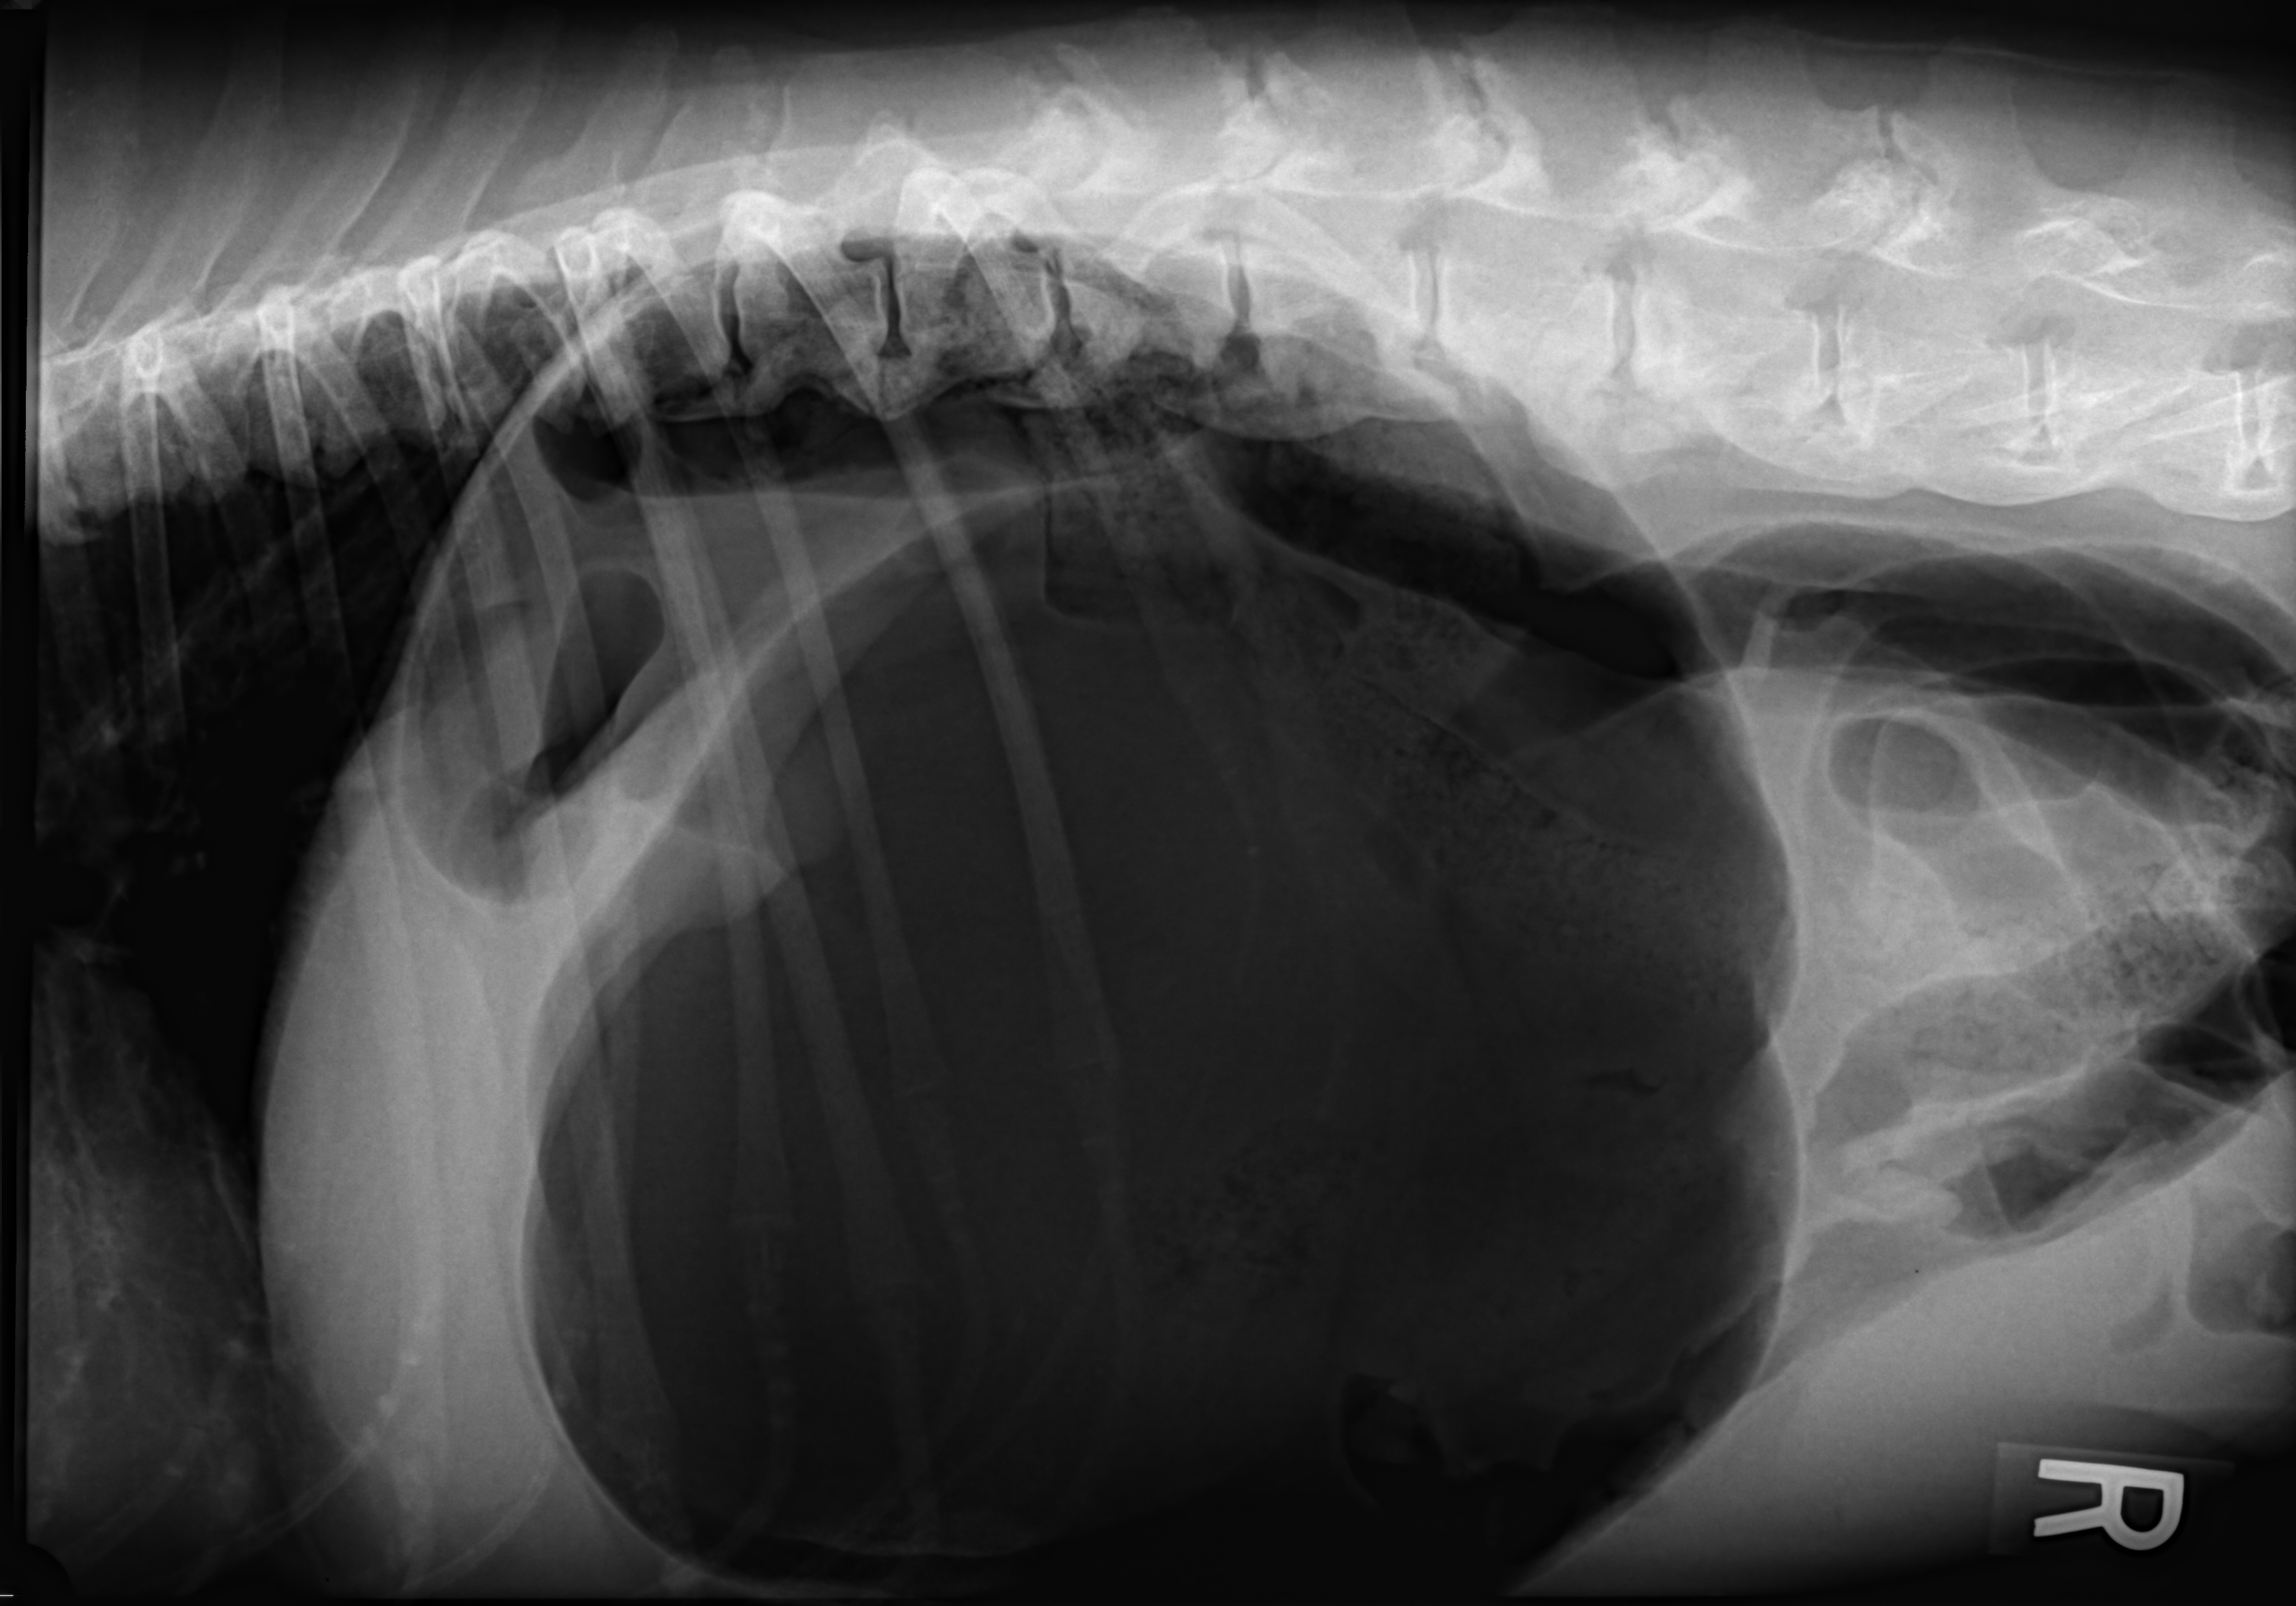

GDV rad Dr Phil Zeltzman’s Blog Can Cats Get Gdv gdv is very rare in cats, most commonly affecting dogs. A definitive cause for gdv has not been. bloat is a condition where a cat’s stomach becomes too full and causes pain, nausea, and bloating. While the exact cause of. It can lead to gastric dilatation volvulus. Can Cats Get Gdv.

Can Cats Get Gastric DilatationVolvulus (GDV)? The Cat Bandit Blog Can Cats Get Gdv gdv is very rare in cats, most commonly affecting dogs. While the exact cause of. It can lead to gastric dilatation volvulus. bloat is a condition where a cat’s stomach becomes too full and causes pain, nausea, and bloating. A definitive cause for gdv has not been. Can Cats Get Gdv.